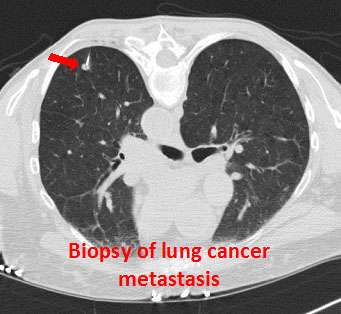

- Chest x-ray

- CT scan

- Biopsy of the lung